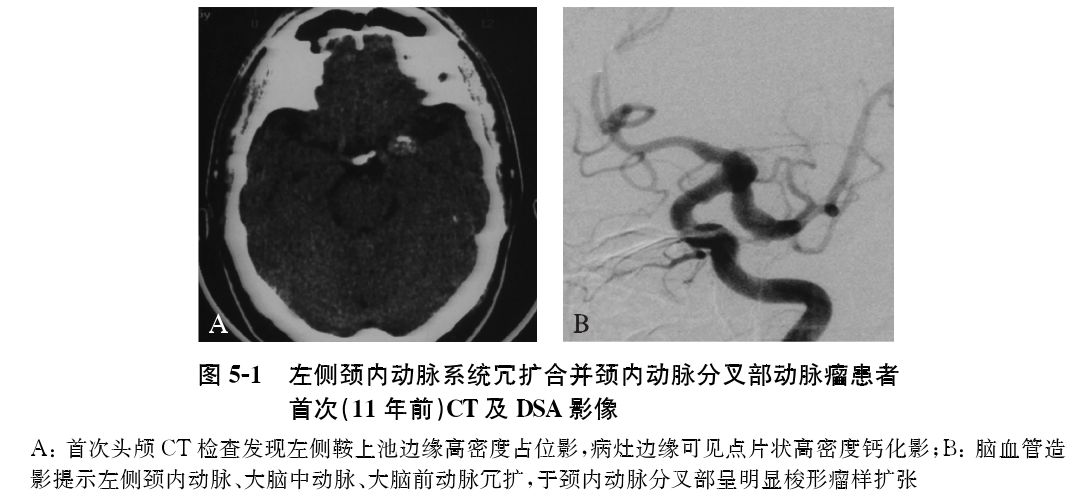

CT:11年前CT检查发现左侧鞍上池边缘高密度影,伴片状高密度钙化影(图5-1A)。

DSA:11年前脑血管造影显示,左侧颈内动脉、大脑中动脉、大脑前动脉冗长扩张(冗扩),于颈内动脉分叉部呈明显梭形瘤样扩张(图5-1B)。